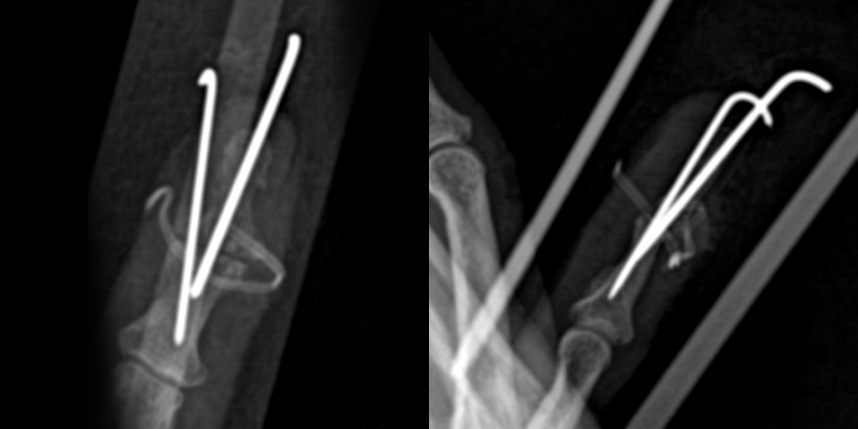

관절 유합술의 경우 “H” 절개를 통하여 관절을 충분히 노출시킨 후 관절 연골을 깨끗하게 제거하여 뼈와 뼈가 직접적으로 맞닿도록 한 후 이를 이용하여 고정합니다. 뼈 손상을 최소화하기 위하여 두 개의 K 강선으로 축고정과 회전고정을 하는 방식을 이용하며 6-8주 째 K 강선을 제거합니다.